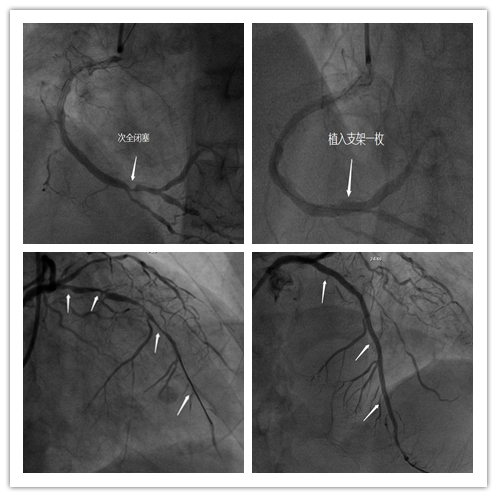

血液净化科与心内二科的专家们反复讨论病情,制定了周密详尽的手术及围术期护理计划,于4月22日进行了冠脉造影术,结果示:前降支弥漫病变,最重95%狭窄。右冠中远端99%狭窄。于5月8日、5月28日两次行冠状动脉支架植入术共植入支架4枚。患者血管钙化严重,原本柔软的血管壁已变得无比坚硬而脆弱,导管在血管中的推送、支架在血管中的扩张都变得更加困难。手术由心内二科赵贵明主任主刀,血液净化科姜晖医生协助,两位医生操作快、准、稳,两次手术均顺利完成。赵贵明主任术后表示:“由于患者的特殊性,导管导丝及支架的型号我们都是精心选择,既满足于患者的病情需求又尽最大可能地降低经济负担,术中用药剂量、手术时间也都要仔细斟酌,在不对肾脏造成过重负担的前提下完成心血管的救治。要从患者的角度出发维护患者的健康,提高患者的生活质量。”